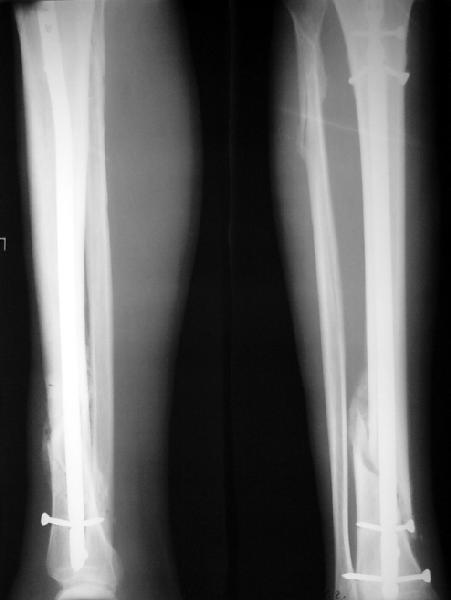

На мой взгляд, на снимках, приведённых Вами - неправильно сростающийся перелом дистальной трети большеберцовой кости, состояние после остеосинтеза интрамедуллярным гвоздём.

Как Вы пишите снимок под номером 1 - менсяц после операции, под номером 2- два месяца после операции.

Установка с медиальной стороны гвоздя в области дистального фрагмента дополнительного шурупа помогло бы Вам репонировать и удержать перелом в анатомическом положении, предотвратило варусную деформацию и смещение по ширине.

На мой взгляд внутрикостная фиксация переломов дистальной и проксимальной трети большеберцовой кости, за исключением поперечных, не очень хорошее решение вопроса, аппарат Илизарова или Тэйлора, позволяющие призвести закрытую анатомическую редукцию и отличное удержание отломков в период сращения.

I think that the X-Rays show S/P IMN of Spiral # of the Distal Tibia consoles in misalignment.

Let to express concerning technique of operation my opinion... Insertion of a screw to medial side of a nail in distal fragment would help you to reduction and to keep this fracture in anatomic position has prevented varus deformity and displacement on width. By the way, if it is possible send a postoperative picture.

In my opinion IMN of fracture distal and proximal thirds of the tibia bones, except for transverse, not so good decision of treatment. Ilizarov or Taylor external fixators allow to the closed anatomic reduction and excellent fixation such fractures during the consolidation period.

А если вспомнить лечение аналогичных повреждений функциональными брэйсами (Sarmiento), там рентгенограммы могут быть еще менее привлекательными, однако результаты вполне приемлемы.